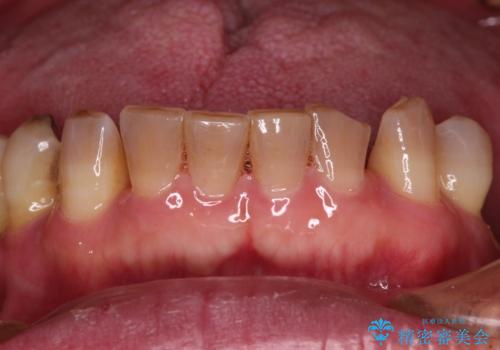

- 奥歯が咬みにくく、前歯がぐらぐらするとのことで来院された患者様です。

咬合力が強く、奥歯が欠損している状態でした。

欠損部はインプラントによる補綴治療を行うこととし、臼歯部が安定した後に、上下前歯部をオールセラミッククラウンにて補綴治療を行うこととしました。

上顎前歯に歯周ポケットの深い部分がありましたが、インプラントの仮歯で奥歯がしっかりと噛めるようになると、1年程度で深い歯周ポケットは解消されました。